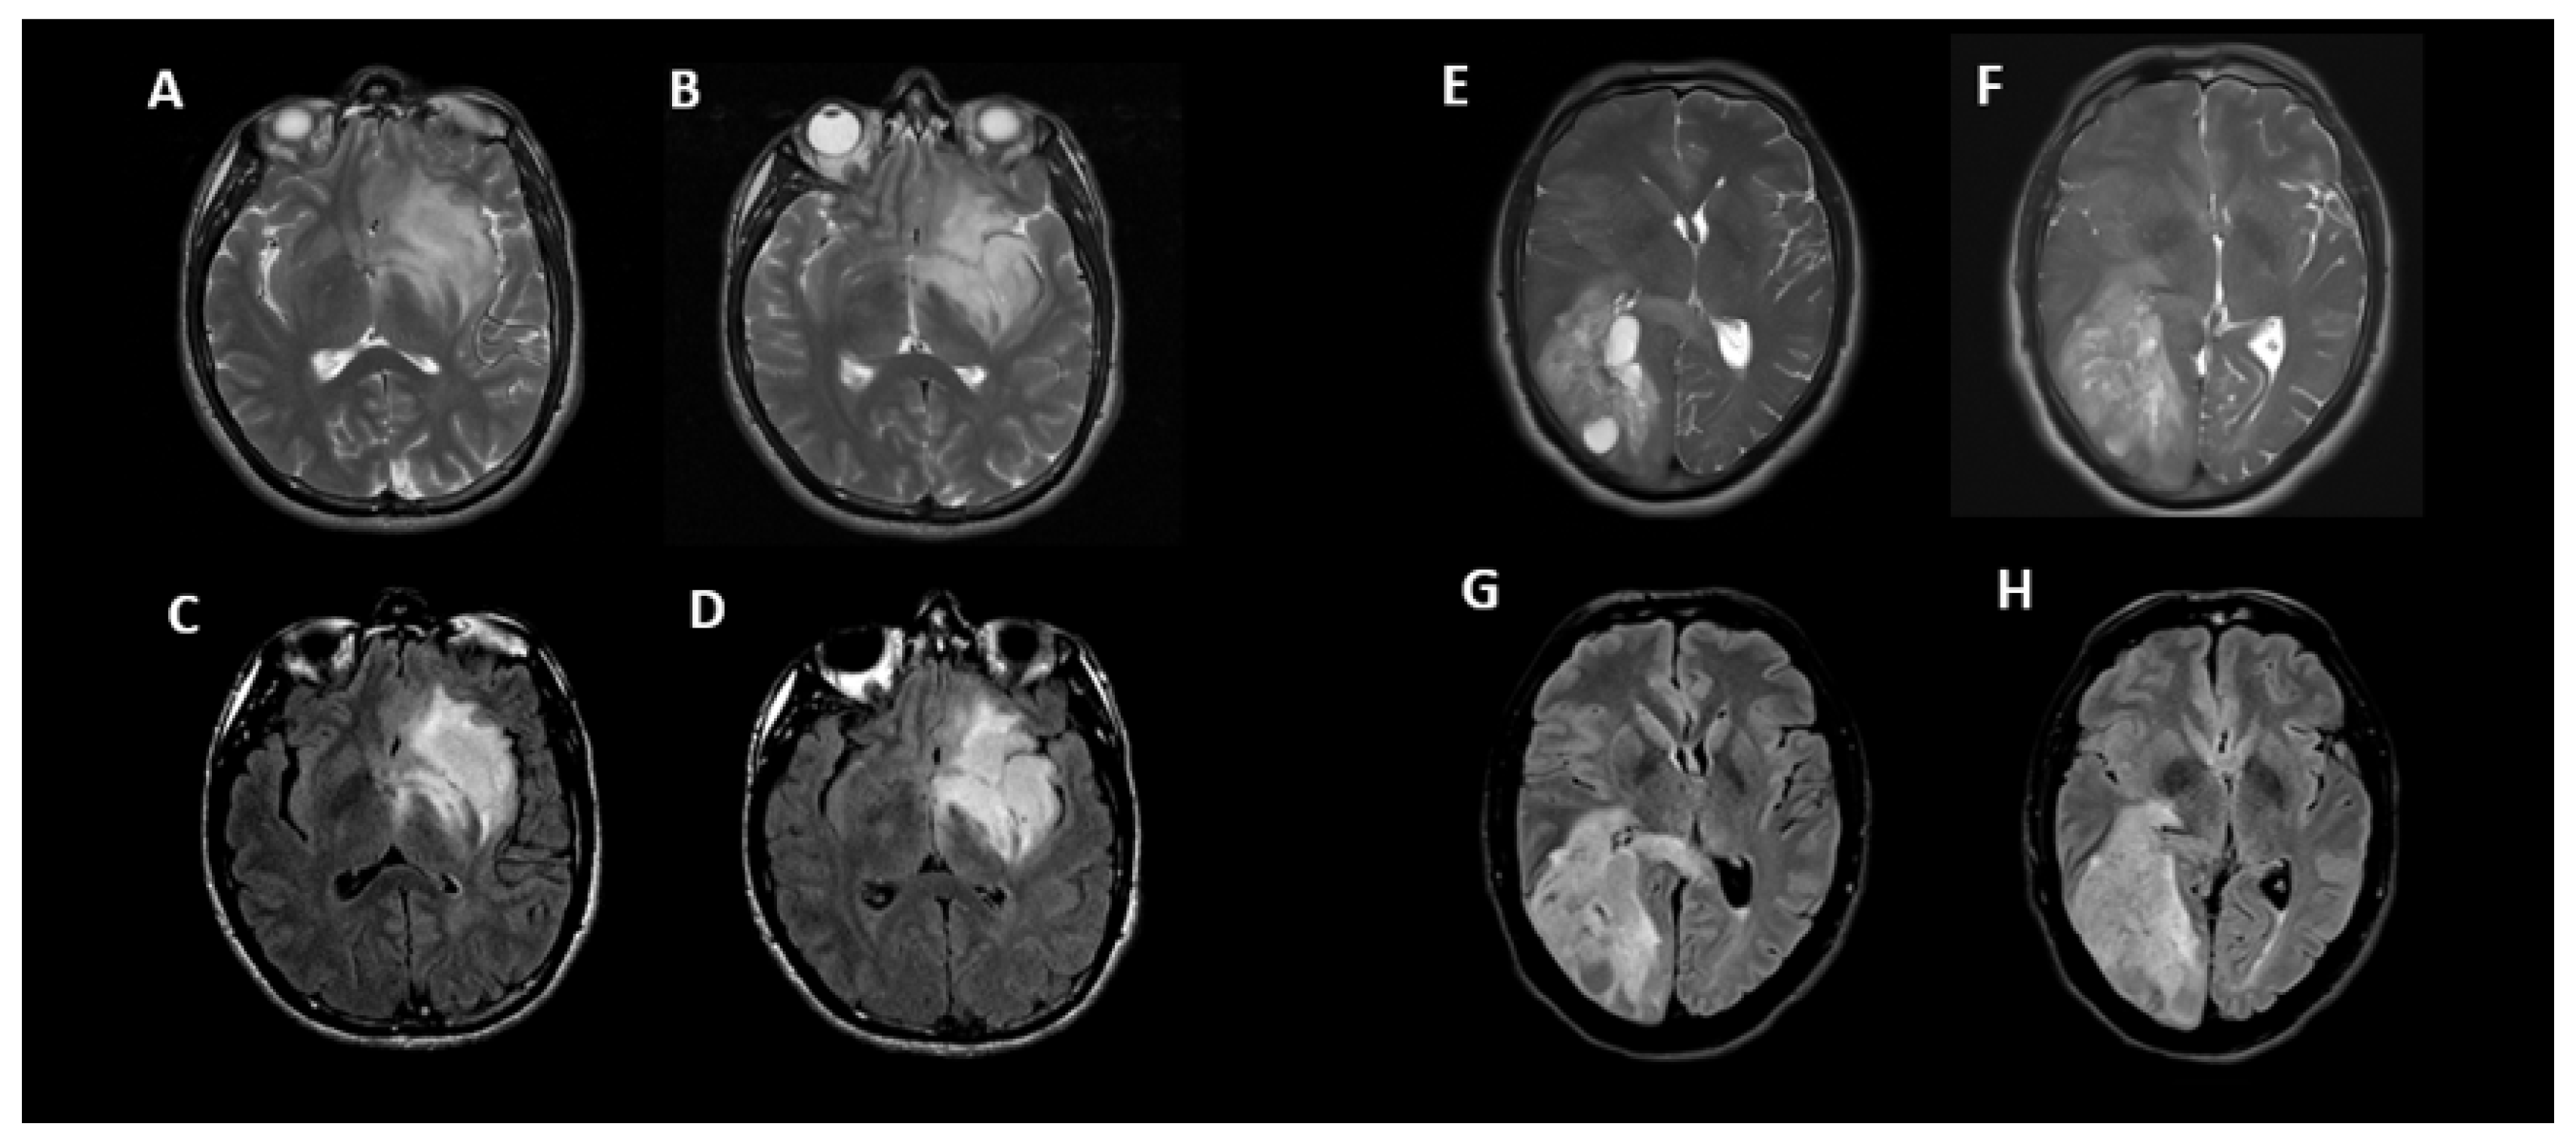

3.2. T2-FLAIR-Mismatch-Based Prediction of 1p/19q Co-Deletion Status